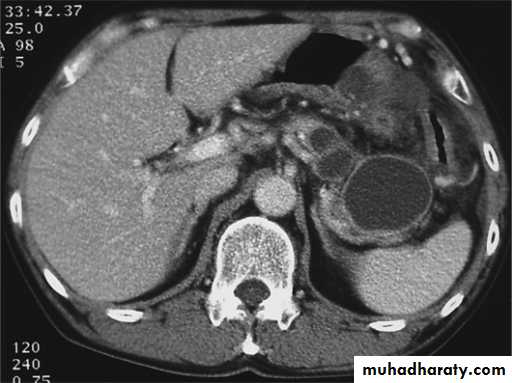

Secondary metastasis in the liver

Multiple rounded hypo density areas of different density , shape & different size .

Pattern of enhancement is either uniform , target or bulls eye pattern .

Hepato megaly .

Secondary metastasis within the liver

CT Scane